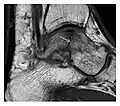

Fatigue fractures are more frequent in women which may be due to the relatively smaller bones of women. Moreover, pregnancy is a well-recognized risk factor for femoral neck fatigue fracture. While fibular and metatarsal fractures have a low risk of complications, other sites including the femoral neck, midanterior tibia, navicular, talar, and other intraarticular fractures are prone to complications such as delayed union, nonunion, and displacement. The site of the insufficiency fracture may be specific to the activity: for example, rugby and basketball players are more prone to navicular fractures, while gymnasts have a higher risk for talar fractures (Figure 7). Long distance runners are at increased risk for pelvic, tibial (Figures 8 and 9), and fibular fractures. In the military, calcaneus (Figure 10) and metatarsals are the most commonly cited injuries, especially in new recruits. Billiard players are at risk for upper limb fractures (Figure 11).[1]

-

a -

b

Figure 7: Fatigue fracture of the talus in a 25-year-old male basketball player with right hind foot and ankle pain, without history of trauma, and a normal initial radiograph (not shown). (a) One-month followup lateral radiograph shows normal appearance. (b) Sagittal T1-weighted MRI shows an irregular fracture line (arrow) within an ill-defined area of hypointensity corresponding to bone marrow edema.[1]